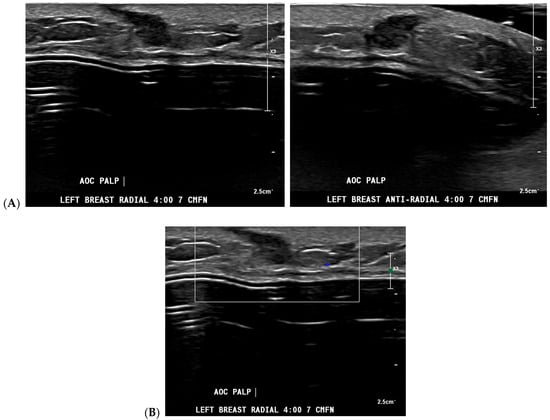

Cancer detection systems typically involve neural networks, machine learning, or deep learning developed from training models to recognize patterns, while diagnostic systems use an additional algorithm to classify [17]. Several CNN models have been developed to correlate ultrasound imaging features of a lesion with the four-classification breast cancer molecular subtypes [42]. Our institution uses Koios, which utilizes machine learning and AI to generate the probability of malignancy of a breast finding by evaluating a region of interest (ROI) selected by a radiologist [3,5]. Ultrasound AI has been found to reduce intra- and interobserver variability and to improve accurate BI-RADS classification of sonographic breast findings [3,5]. Ultrasound AI can also increase CDR [5] and reduce the number of unnecessary biopsies [5,43,44] (Figure 1, Figure 3, and Figure 4).

Figure 3.

A new cancer diagnosis appropriately classified as “malignant” by artificial intelligence (AI): This patient in her 40s with a history of left breast carcinoma diagnosed 1 year prior, status post-left mastectomy with chemotherapy and hormonal therapy, presented with a palpable abnormality in the superficial lower outer left breast. No new or suspicious findings were seen on the patient’s diagnostic mammogram. Correlating with the patient’s concern about a palpable lump, diagnostic ultrasound revealed an irregularly shaped, hypoechoic mass with angular margins that are non-parallel (A), and Doppler shows no vascularity (B). The AI program Koios recognized this mass as “Probably Malignant” (C). This was returned as biopsy-proven invasive ductal carcinoma. Images obtained from the Icahn School of Medicine at Mount Sinai.